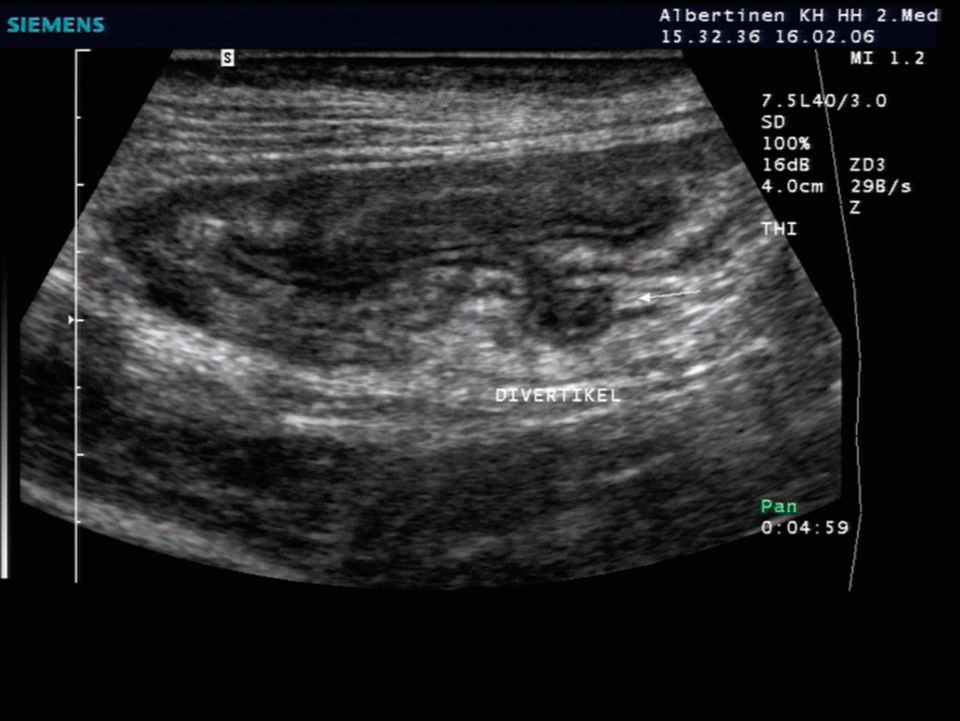

Hier ragt ein kleines Divertikel aus dem Kolon. Hier ragt ein kleines Divertikel aus dem Kolon. © Albertinen-Krankenhaus Hamburg/sonographiebilder.de